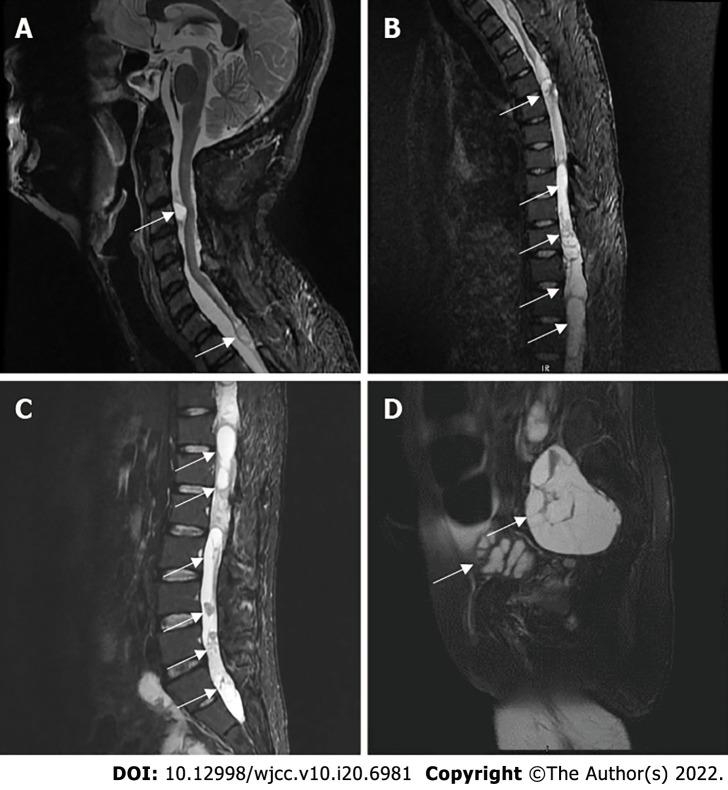

A 40-year-old male had multiple masses all over his body, starting at the age of 19. Four years prior, he started to experience a progressive decrease in muscle strength in both lower limbs and developed urinary and defecation dysfunctions, and gradual paralysis. One month prior, the patient developed pain and numbness in his left forearm. The patient had undergone five surgical procedures for this disease in our department. Based on the family history, imaging examinations, pathological biopsy and molecular biological examinations, the diagnosis of schwannomatosis was confirmed. This time, the patient was admitted to our hospital again for a 6th operation because of the pain and numbness in his left forearm. After the operation, the patient's symptoms improved significantly; the patient recovered and was discharged from the hospital. At the last telephone follow-up, the patient reported a poor general condition but was alive.